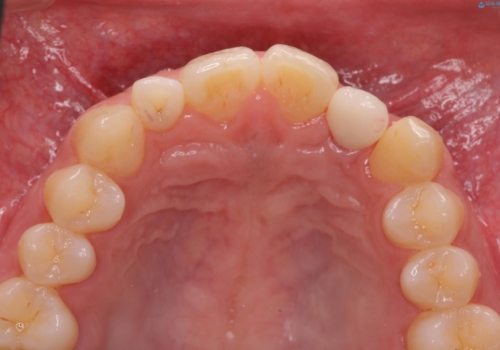

前歯部 インプラント治療

それぞれの治療に特徴がありますが、取り外しの必要がなく隣の歯を削る必要も必要ないインプラント治療を選択されました。

前歯部にインプラントを埋入し、きれいに仕上げるためには骨の造成技術や歯肉の厚みを増すような処置を行い、インプラント周囲の環境を整備することが肝要です。